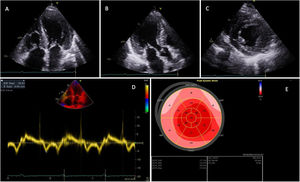

Transthoracic echocardiogram in a patient with transthyretin amyloid cardiomyopathy. (A–C) Left ventricular (LV) hypertrophy with a sparkling pattern of the myocardium on the two-dimensional transthoracic echocardiogram in 4-chamber (Video 1) (A), 3-chamber (Video 2) (B) and parasternal short-axis (Video 3) (C) views; (D) mitral annular tissue Doppler imaging, showing LV diastolic dysfunction with reduced septal e′ velocity (5 cm/s) and increased E/e′ ratio (20.9); (E) LV bullseye plot with peak systolic global longitudinal strain, showing an apical sparing pattern.

Nevertheless, the proposed echocardiographic criteria of cardiac involvement by ATTR amyloidosis differ significantly between medical societies8,120 (Table 12). The 2021 US expert consensus recommendations propose as evidence of cardiac involvement by amyloidosis any of the following: LVWT >12 mm, apical sparing, or grade 2 or 3 diastolic dysfunction.120 By contrast, the 2021 European position statement proposed a combination of unexplained LVH (≥12 mm) with at least two additional echocardiographic findings (grade 2 or 3 diastolic dysfunction, 5-5-5 sign or GLS <−15%) or a multiparametric echocardiographic score of ≥8.8